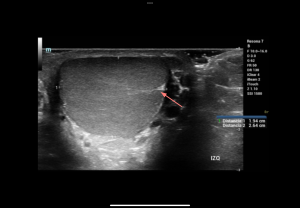

Testicular trauma

Integrity of the tunica albuginea determines management:

- Testicular fracture: Intact tunica albuginea, linear hypoechoic band, preserved peripheral flow.

- Testicular rupture: Disrupted tunica albuginea with parenchymal extrusion, heterogeneous echotexture, absent/reduced flow.